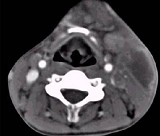

- 单项选择题男性,67岁, 颈部出现疼痛性肿块半年余,CT扫描如图所示, 最可能的诊断是 ( )